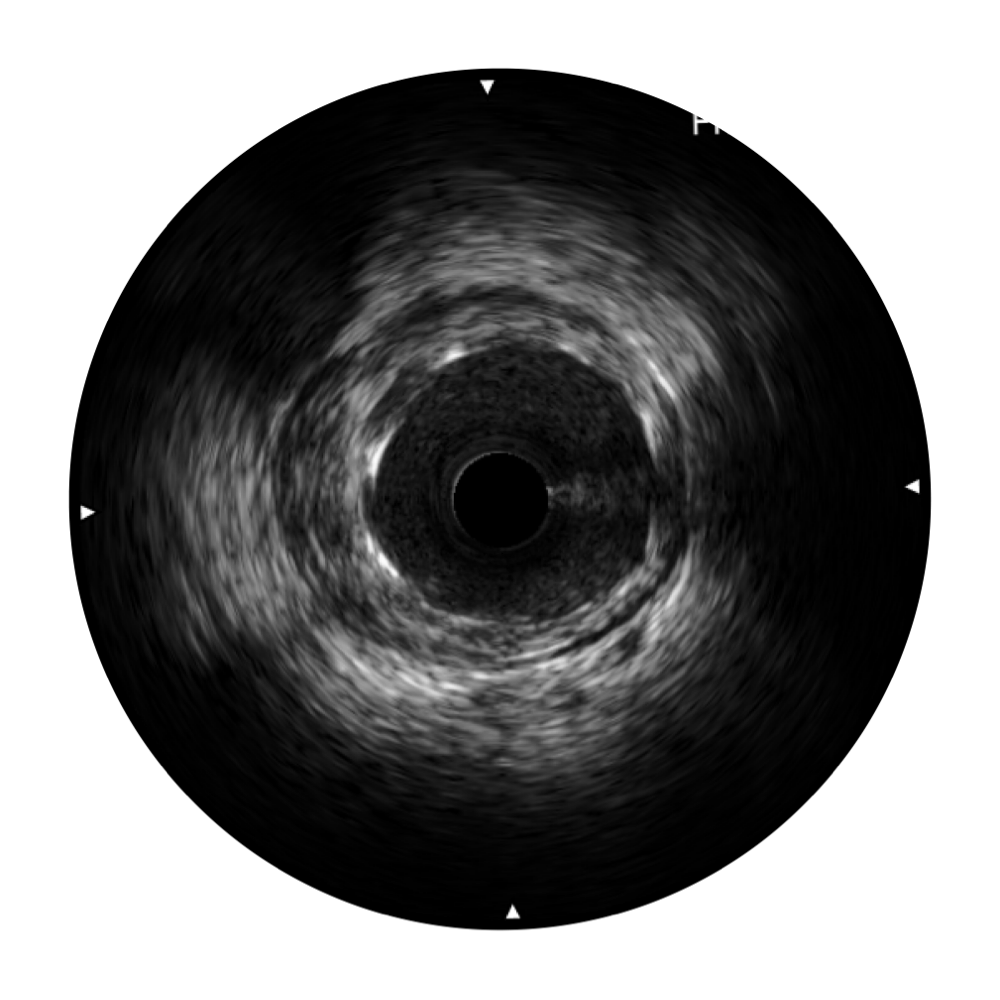

血管内超声(IVUS) 通过对病变程度、性质和累及范围的精确判断,可帮助选择治疗策略和方法,指导介入治疗过程,能够降低主要不良心血管事件,改善预后,在复杂病变介入治疗中用于指导支架置入的优势更为明显。血管内超声(IVUS)已成为精准心血管介入治疗的“金标准”。

环球UG官网始终关注未满足的临床需求:超宽频成像技术同时提供高清分辨力和充足穿透深度,适应不同血管结构的治疗引导;智慧赋能,简化操作,降低临床应用难度和缩短学习曲线。

环球UG官网超宽频成像技术覆盖20-80MHz1或20-90MHz2频率范围, 提供优异的分辨力同时也保证充足的穿透深度

对比传统IVUS导管成像,环球UG官网宽频IVUS图像的近场支架梁显影更细腻,远场中膜外血管仍清晰可辨,兼顾远中近,兼顾分辨力与穿透深度